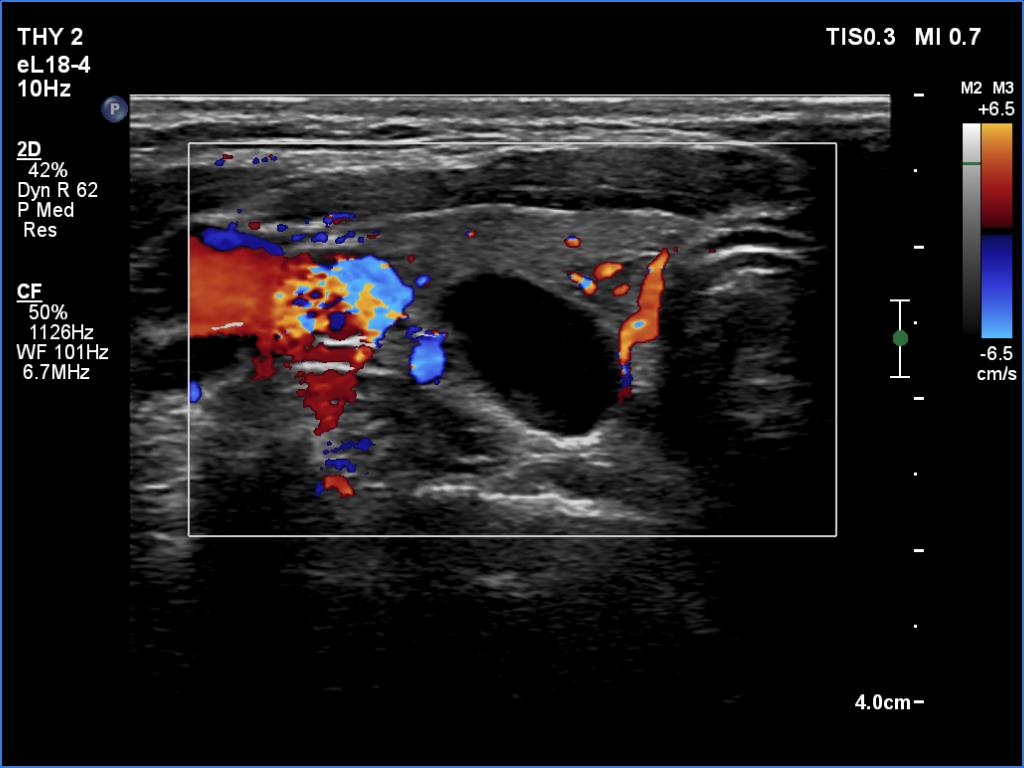

Ultrasonography. The thyroid was echonormal. There were several small hypoechoic areas in both lobes and a cystic nodule in the right lobe. At first sight the nodule seemed to be a pure cyst. However, thorough analysis revealed a tiny echonormal solid area in the dorsal part of the lesion. Therefore, this nodule does not meet the criteria of a pure cyst. The lesion presented taller-than-wide shape.

2. If we detect any solid part within an almost completely cystic nodule than the lesion should not describe as a pure cyst. Indeed, this cyst belongs to the peripheral-type subgroup.

3. This case illustrates one of the most important limitations of taller-than-wide shape. A nodule inevitably follows the anatomy. The cartilage of the trachea hinders the horizontal spread, therefore the only remaining route for the nodule is to extend in the perpendicular direction.

4. The cystic lesion can be regarded as EU-TIRADS 2 or EU-TIRADS 3 nodule, depending on the judgement of the uncertain structure at the cystic wall. Nor can it be ruled out to classify the lesion as EU-TIRADS 5 due to the nonparallel orientation. However, it is more rational and in the best interest of the patient to classify the lesion as EU-TIRADS 2.